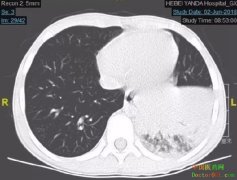

• [媒体发稿] 重症肺炎患儿 在燕达医院儿科康复出院 日期:2018-06-28 22:08:45 点击:153 好评:0

肺炎是一种严重的肺部感染,常见症状包括咳嗽、呼吸急促或困难、发热、食欲下降等,部分婴儿仅有精神食欲差、口吐白沫的症状。儿童处于生长发育期,免疫功能不健全,免疫球蛋白含量较低,易发生感染,3岁以内婴幼儿是肺炎的高发人群。 重症肺炎是一种严重甚至致死...